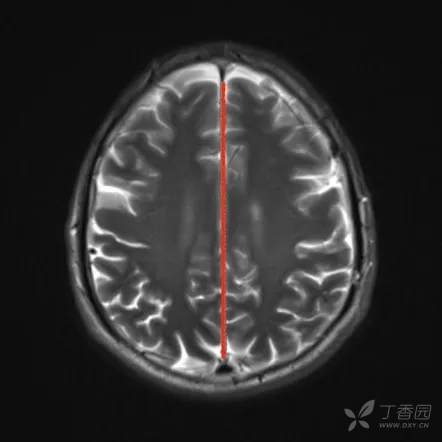

大脑纵裂池

大脑纵裂池 cistern of cerebral longitudinal fissure (interhemispheric fissure cistern)位于两侧大脑半球之间的大脑纵裂内,内有大脑镰插入,故此池分为左右两部。

该池底部绕于胼胝体周围,称为胼胝体体周池,向前下延为终板池,向后下续于大脑大静脉池。

大脑纵裂池在不同横断面上的表现各异。例如,在胼胝体以上层面中所见为大脑纵裂池全长;在胼胝体出现的层面上大脑纵裂池分为前后两段,分别位于胼胝体断面的前后方;在较低的鞍上池层面则只见大脑纵裂池前段。

CT

MRI T2